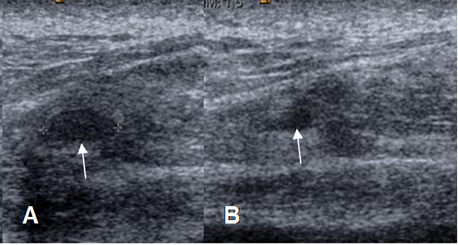

Fig 16 A. Distensión muscular grado 2.

A y B: Ecografía. Areas de solución de continuidad en las fibras musculares, por lesión grado 2.

Fig 16 B. Distensión muscular grado 2.

A y B: Ecografías. Lesiones ovaladas, heterogéneas y de bordes definidos, dentro de las fibras musculares por ruptura parcial.